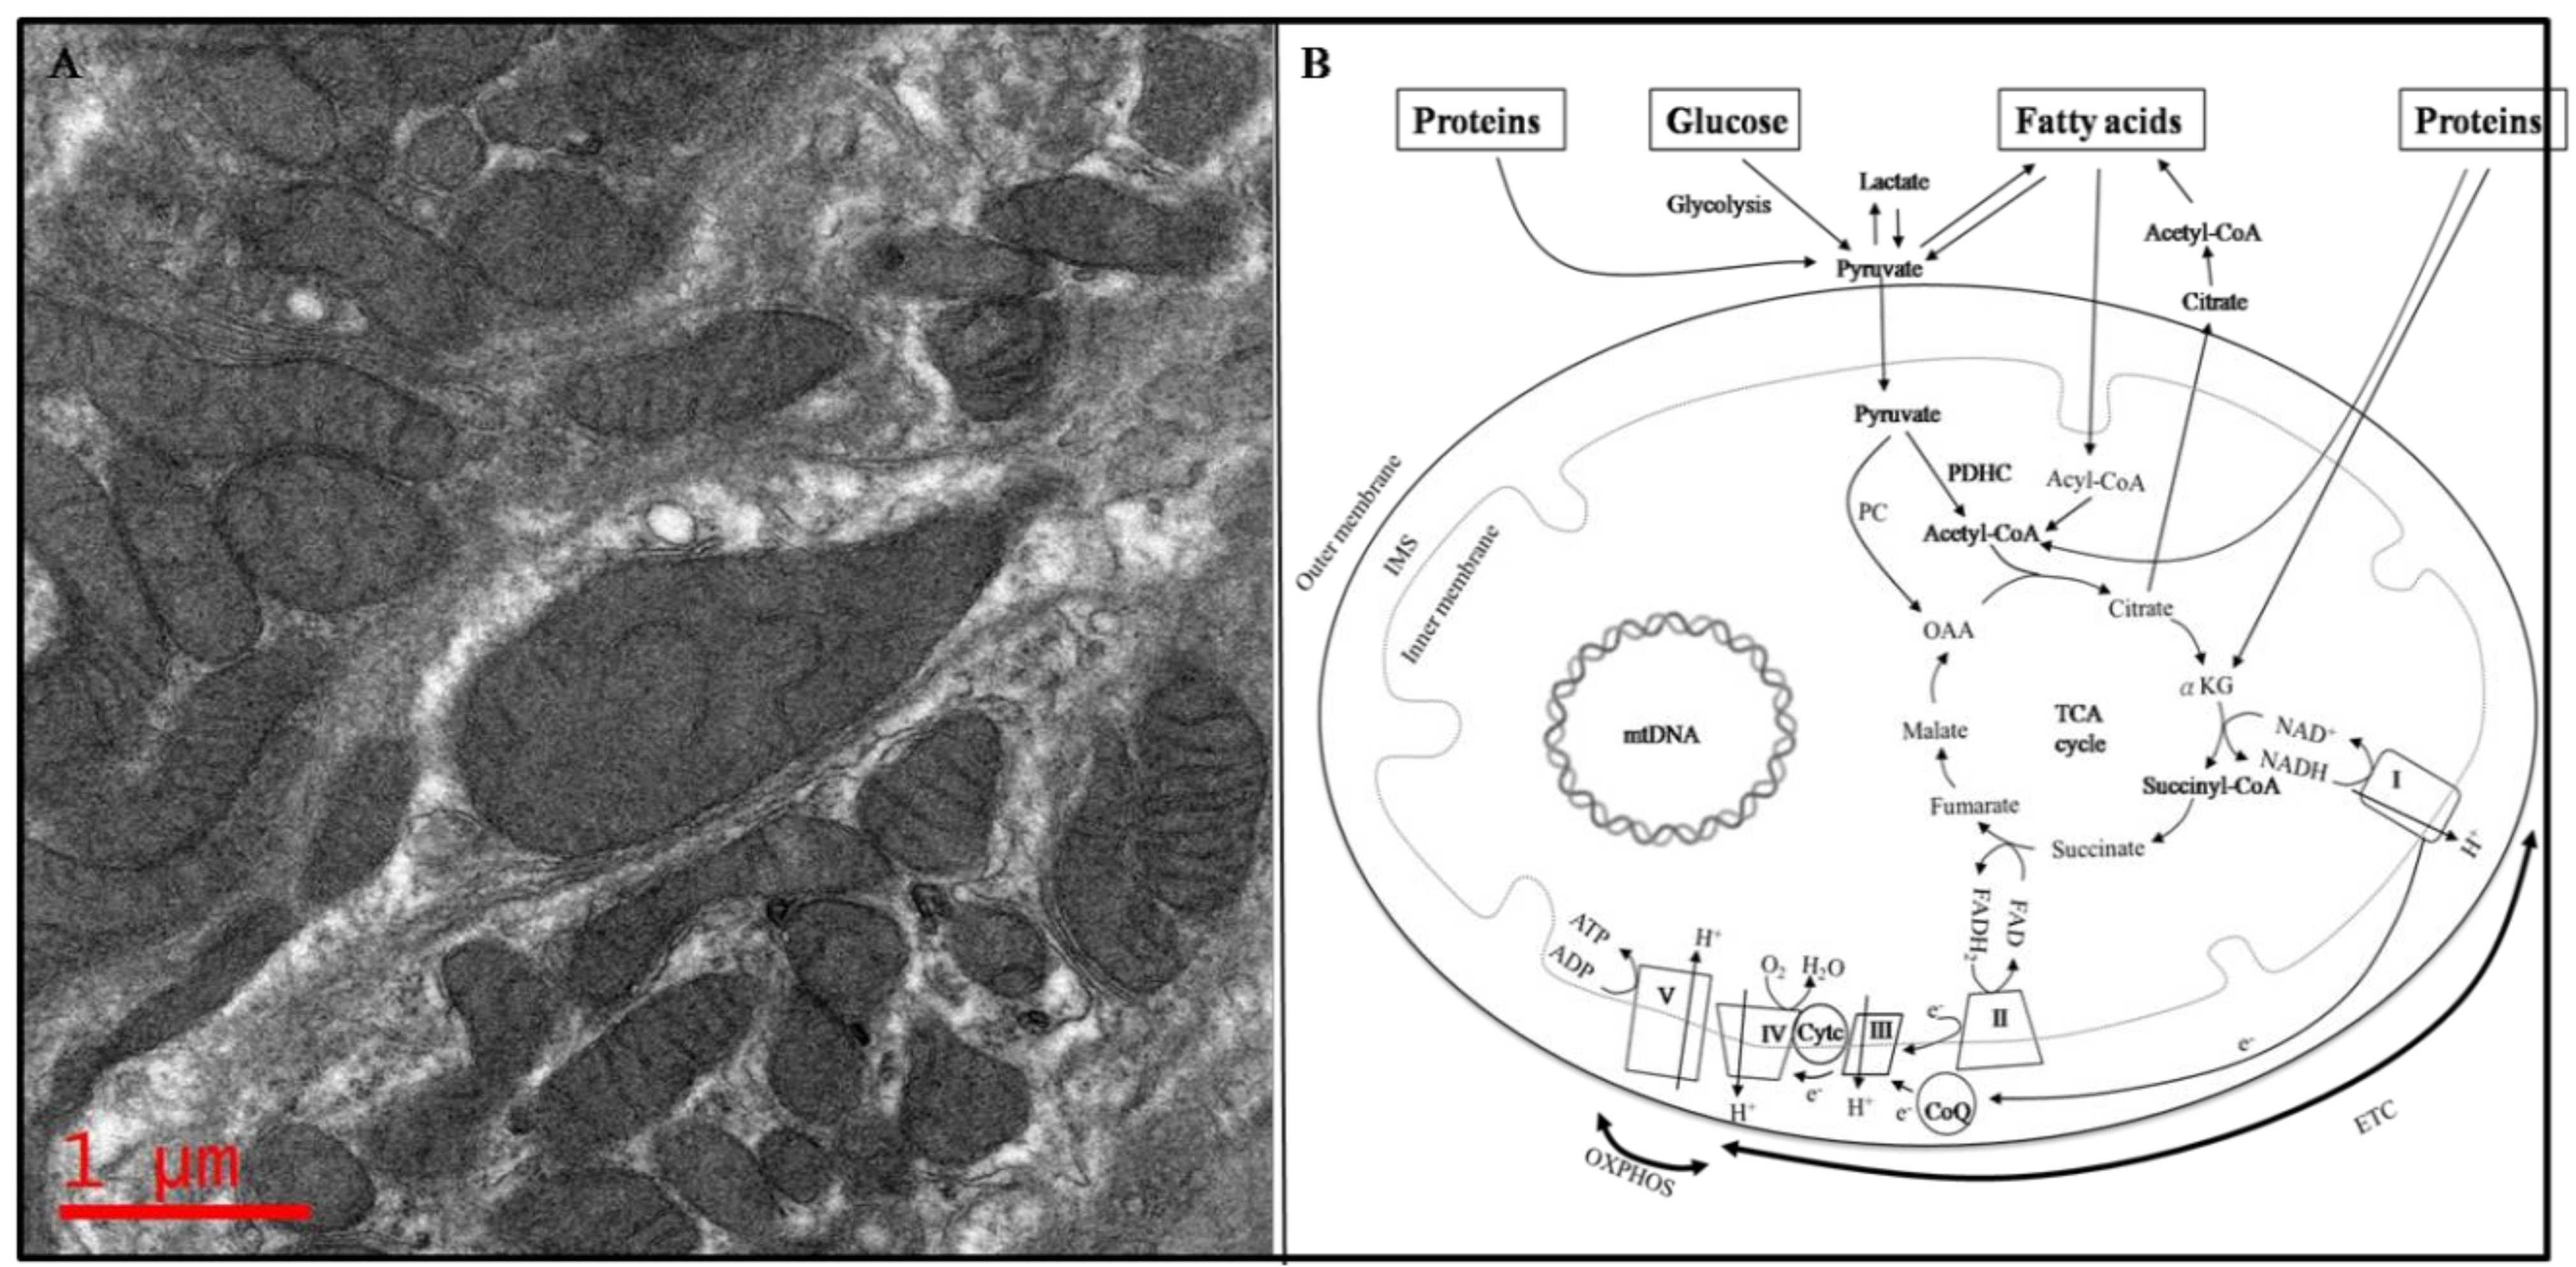

1. Introduction of Mitochondria

1.1. Structure of Mitochondria

1.2. Mitochondria, the Powerhouse of the Cell